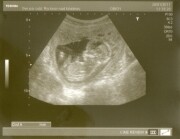

Ahoj, s přítelem čekáme děťátko, termín porodu máme 23.7.2011. Moc se na něj těšíme, je to malý raubíř a bude se jmenovat po tatínkovi Jakub :)